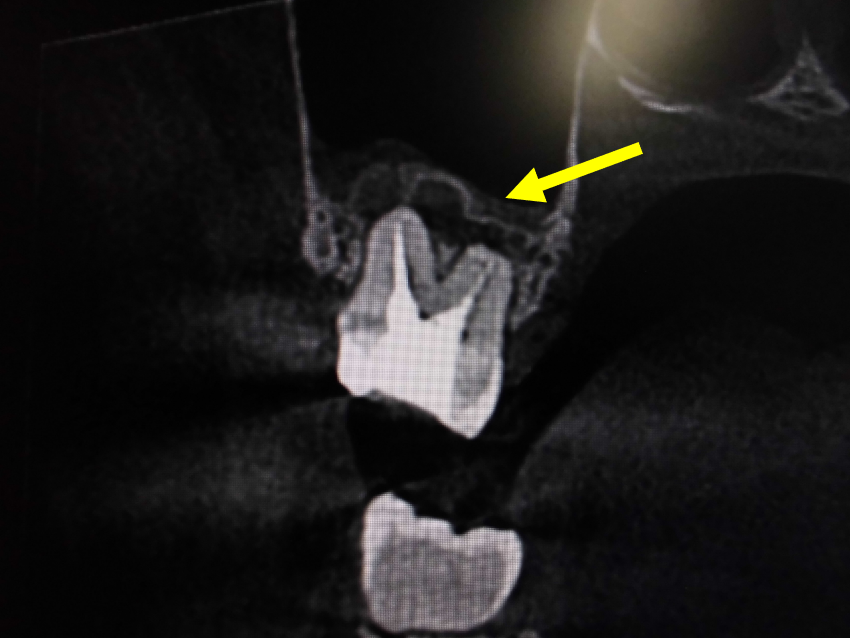

左上奥歯が割れています。一般的なレントゲンではわかりません。

CTでは破折線がはっきり見えます。患者様も納得しやすいです。